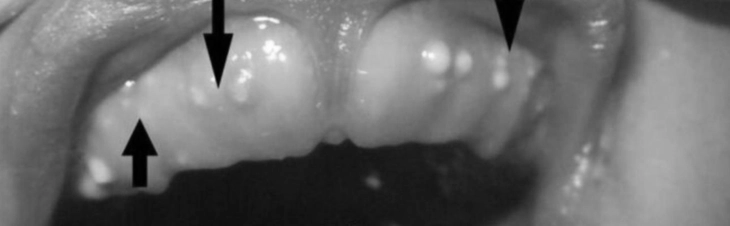

Điểm chung của ba dạng tổn thương này là đều chứa keratin bên trong, có màu trắng hoặc vàng nhạt, kích thước vài milimét, thường 1-3mm, không đau, và tự mất sau vài tuần đến vài tháng.

Ở trẻ sơ sinh, nang lá răng xuất hiện dưới dạng các tổn thương lành tính chứa đầy keratin, hình thành từ phần biểu mô còn sót lại của lá răng – một cấu trúc biểu mô tham gia vào quá trình hình thành răng ở giai đoạn hình chuông. Chúng thường nằm trên đỉnh sống hàm, cả hàm trên hoặc hàm dưới, và thường xuất hiện thành nhiều sẩn nhỏ màu trắng hoặc vàng nhạt.